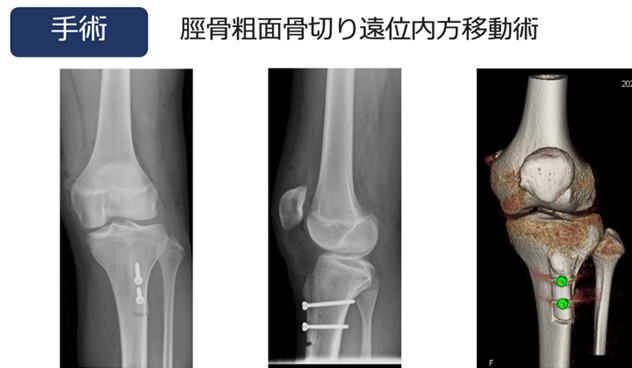

反復性膝蓋骨脱

膝蓋骨脱臼とは大腿骨(太ももの骨)に対して膝蓋骨(膝のお皿)がはずれる状態です。外側の脱臼がほとんどで、内側の脱臼は非常にまれです。

外傷以外に膝蓋大腿関節(太ももと膝のお皿の関節)の先天的な形態異常、全身の関節弛緩性、軟部組織のバランス異常など、さまざまな素因により膝蓋大腿関節の適合性が悪く、膝蓋骨が外側にずれてしまっていることが病態の背景としてあります。初回の脱臼は10歳代の女性が生じることが多く、その後繰り返し脱臼をきたすと反復性膝蓋骨脱臼へと移行します。ジャンプ着地や膝を捻る動作などで、膝蓋骨(膝のお皿)がはずれそう、もしくは、はずれる感覚を自覚します。

受傷後は、膝痛や膝に力が入らない、膝がガクッとするなどの症状(Giving way)が出現します。新鮮例では膝の痛みや腫れが生じますが、自然に整復されることが多いです。最初の脱臼以後、脱臼を繰り返すようになると痛みや腫れなどよりも、膝の不安定感が強くなり、スポーツ活動のみならず日常動作でも支障をきたします。

急性期や脱臼の程度が軽いものでは、筋力トレーニングや脱臼を予防するためのサポーターを用いた保存療法を行います。反復性脱臼や、初回脱臼でも脱臼しやすい素因が明らかで、膝の不安感が強く、反復性脱臼になる可能性が高い場合には、手術療法が適応となります。

近年、脱臼を繰り返すことで、脱臼の防止に重要な役割を果たしている内側膝蓋大腿靭帯(MPFL)が破綻すること、および反対に外側支帯の拘縮が生じることが知られており、当院では積極的に外側支帯の切離術およびMPFLの再建術を行っています(図5)。また必要に応じて骨切り術を行うこともあります(図6)。